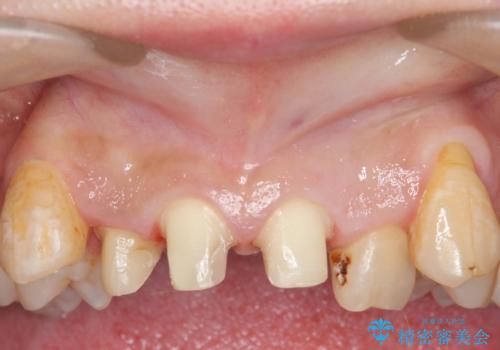

オールセラミッククラウン 長期間放置してきた前歯の虫歯治療

- 上顎前歯の見た目が気になるのでセラミックにしたいといらっしゃった方の症例です。

右上2は歯の神経が死んでおり、根尖病変を認めたため根管治療を行いました。

その後右上1,2番目及び左上1番目の歯に対してオールセラミッククラウンによる補綴を行いました。